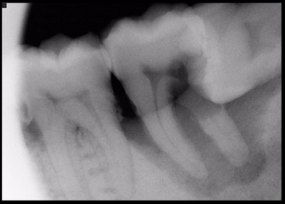

Radiographs